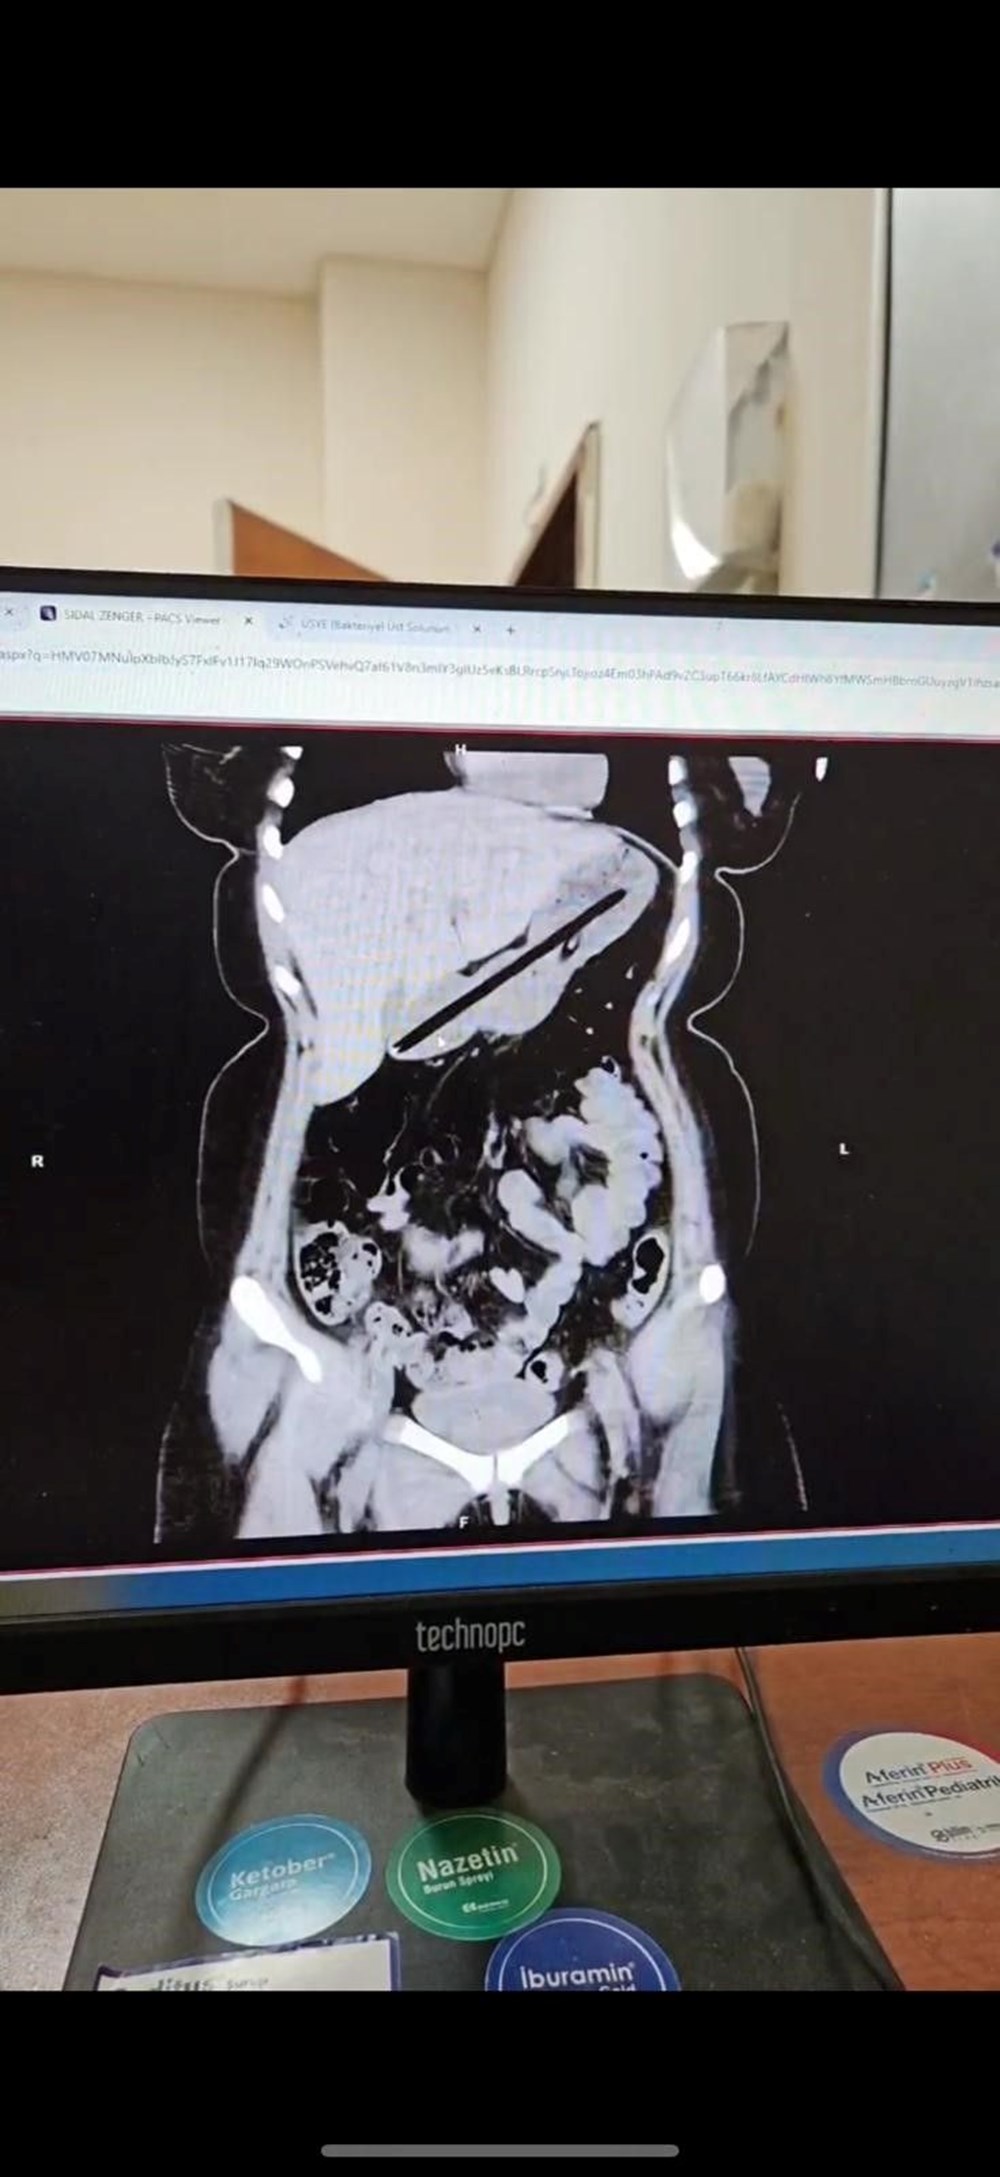

Hastanın midesinde yabancı cisim tespit edildi. Genel Cerrahi ekibince ertesi gün gerçekleştirilen yaklaşık bir buçuk saat süren endoskopi operasyonuyla genç kadının midesinden biri kurşun, diğeri tükenmez olmak üzere iki kalem çıkarıldı. Başarıyla sonuçlanan operasyonun ardından hasta bir gün müşahede altında tutularak taburcu edildi.

Operasyonu gerçekleştiren Dr. Öğretim Üyesi Adem Aslan, ilk kez böyle bir vakayla karşılaştıklarını belirterek, "22 yaşındaki bayan hastamız kalem yutma şikayetiyle ilçe devlet hastanemize başvurmuştu. Tomografisinde midesinde yabancı cisim olduğu görüldü. Biz de tetkiklerimizde midesinde kalem olduğunu gözlemledik.

Daha önce toplu iğne, kemik parçası gibi yabancı cisimlerle karşılaşıyorduk ama bu kadar uzun ve ince bir cisim ilk kez karşımıza çıktı. Midenin boşalması için bir gün bekledik ve ertesi gün yaptığımız endoskopide hastanın bir değil iki kalem yuttuğunu gördük